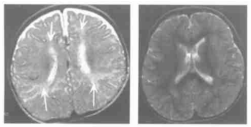

图4.23周BH4D患儿,左图T2WI示额、枕叶髓鞘发育延迟。右图为治疗1年后该患儿的髓鞘发育情况,显示髓鞘发育达到正常同龄儿的水平[2]